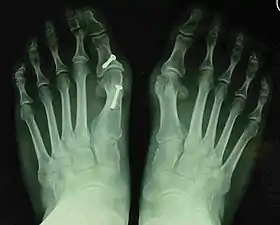

Before_syndesmosis_surgery

Fig. 4a: Before surgery

2_years_after_syndesmosis_surgery

Fig. 4b: 2 years after surgery

Technique

Syndesmosis procedure addresses specifically the two fundamental problems of metatarsus primus varus deformity that gives rise to the bunion deformity. They are leaning and instability of the first metatarsal bone . Syndesmosis procedure uprights the leaning first metatarsal bone with strong binding sutures between it and the second metatarsal bone (Fig. 2) and then also stabilizes it uniquely by creating a fibrous connecting bridge between these two bones (Fig. 3, 4). First metatarsal bone can be readily realigned because by definition of the metatarsus primus varus deformity its first metatarsal is abnormally loose and mobile.